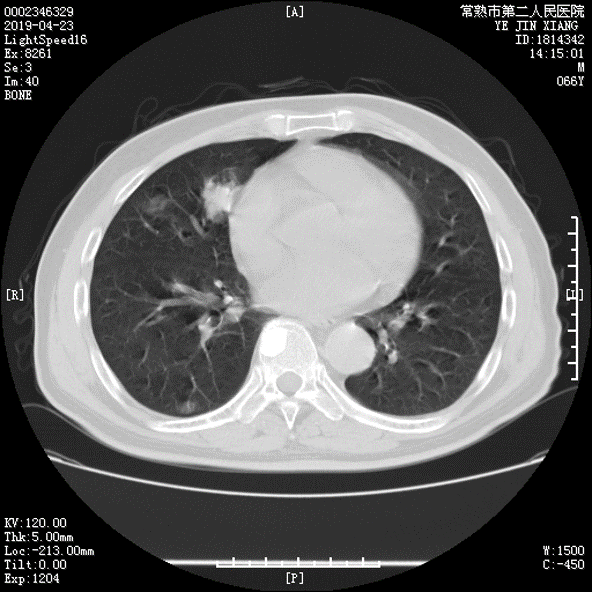

u2019-4-23复查CT提示病情进展,2019.5.5起予贝伐单抗+FOLFOX方案治疗,末次2019.6.16。

2019-07-16口服瑞格菲尼120mg qd,复查CT:双肺转移灶较前明显缩小。

2019-9-9: